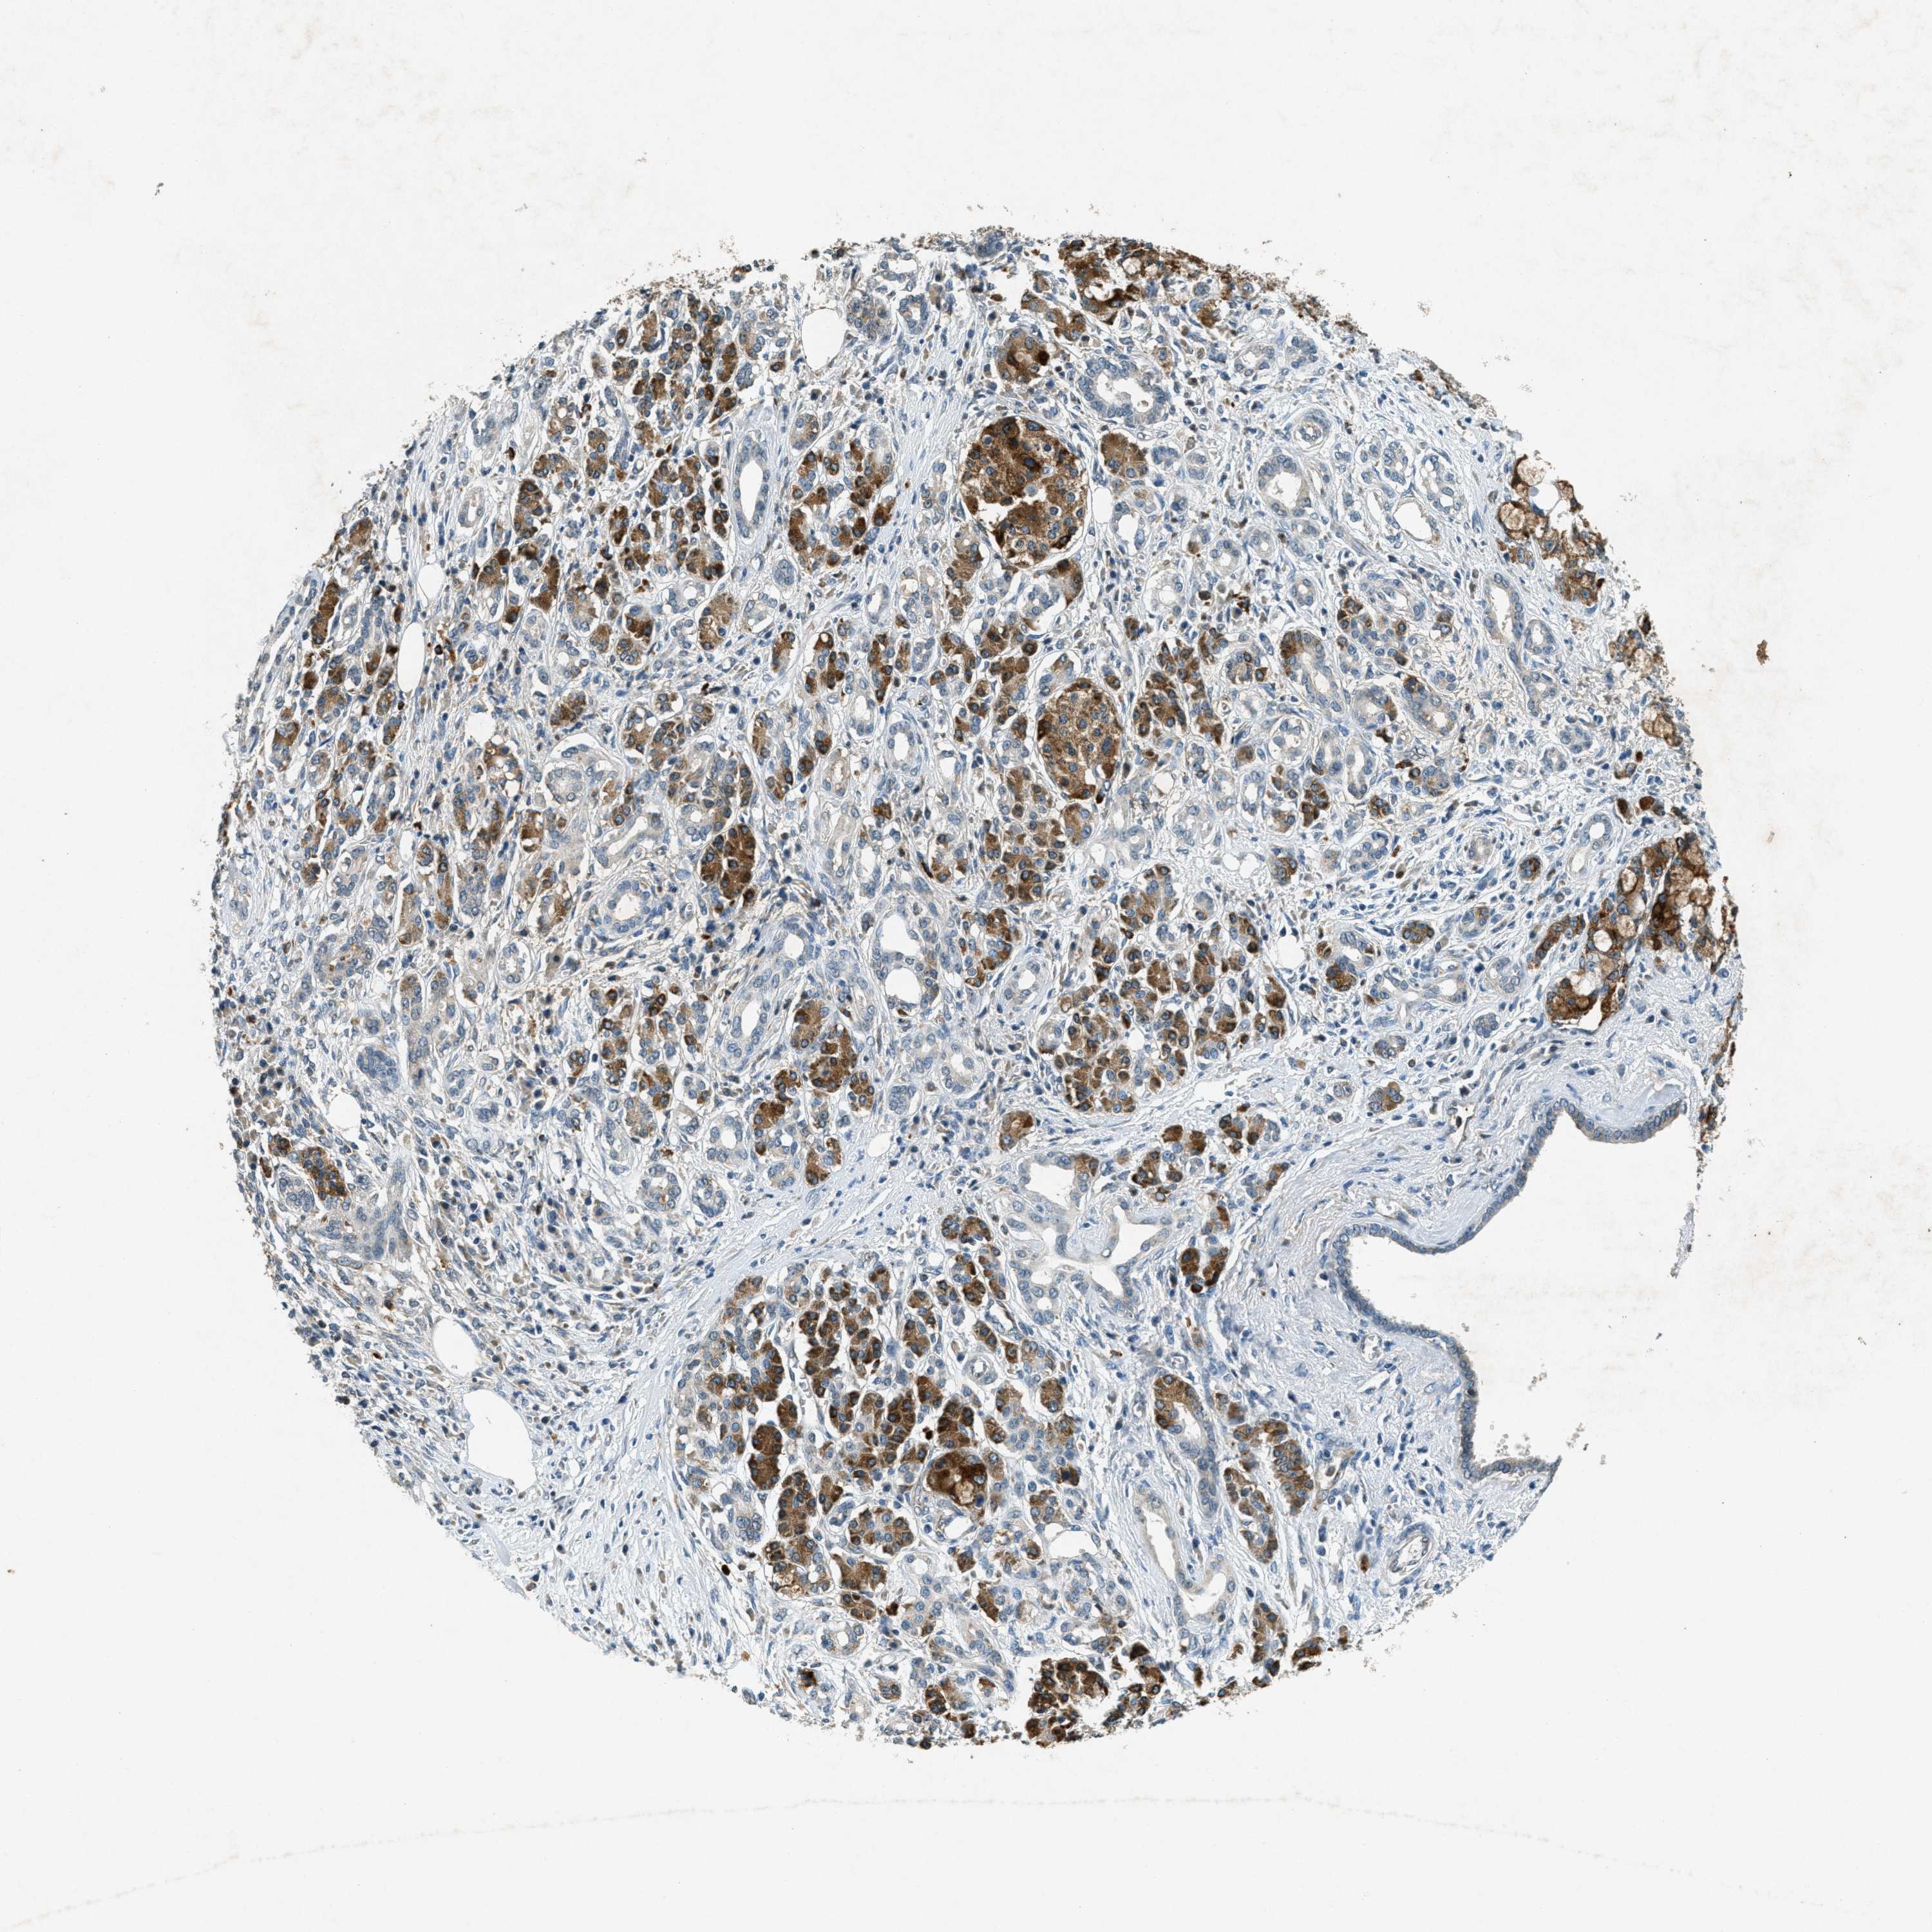

PANCREATIC CANCER - Protein expressioni

A mouse-over function shows sample information and annotation data. Click on an image to view it in a full screen mode. Samples can be filtered based on level of antibody staining by selecting one or several of the following categories: high, medium, low and not detected. The assay and annotation is described here.

Note that samples used for immunohistochemistry by the Human Protein Atlas do not correspond to samples in the TCGA dataset.

Antibody stainingi

Antibody staining in the annotated cell types in the current human tissue is reported as not detected, low, medium, or high, based on conventional immunohistochemistry profiling in selected tissues. This score is based on the combination of the staining intensity and fraction of stained cells.

Each image is clickable and will lead to virtual microscopy that enables deeper exploration of all samples and also displays staining intensity scores, fraction scores and subcellular localization as well as patient and tissue information for each sample.

Antibody CAB018067

Staining

High

Medium

Low

Not detected

Intensity

Strong

Moderate

Weak

Negative

Quantity

>75%

75%-25%

<25%

None

Location

Nuclear

Cytoplasmic/membranous

Cytoplasmic/membranous,nuclear

Adenocarcinoma, NOS

Adenocarcinoma, metastatic, NOS